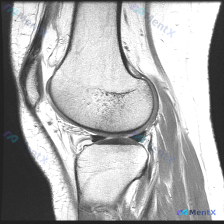

看到这个很有代表性的读片病例,整理出来和大家分享,这个临床-影像不匹配的情况其实临床工作中挺常见的。 病例基本信息 本次分析基于一张膝关节矢状位T1加权磁共振图像,临床提示存在「chondral abnormality(软骨异常)」,无其他病史、体征或检验结果提供。 影像基本观察(单张T1序列) 先...

看到一个有意思的影像读片问题,整理了完整的分析思路分享给大家。 病例/影像基本信息 这是一张单幅膝关节矢状位T1加权MRI影像,问题是观察图像中是否存在软骨异常。 影像本身特点:图像有明显噪声(颗粒感重),对比度一般,解剖结构轮廓可辨认,但精细细节分辨率受限,属于质量不佳的单幅影像。 系统性影像观察...

整理了一份很有参考意义的影像读片病例,核心问题是:这张膝关节MRI-T1序列矢状位图像上,能观察到软骨异常吗?把整个分析思路分享给大家。 一、影像基础信息 这是一幅标准的膝关节矢状位T1加权像,图像对比度良好,骨髓腔呈正常高信号(脂肪髓),皮质骨呈低信号,解剖结构显示清晰,无明显运动或金属伪影;图像...

遇到一个挺典型的读片问题,整理出来和大家分享一下思路: 病例背景 临床关注点:怀疑膝关节软骨异常,提供单张膝关节MRI矢状位T1加权像(T1WI)读片 影像基础评估结果 先把影像上能看到的情况理清楚: 1. 骨性结构:股骨远端、胫骨近端皮质连续,没有骨折;骨髓信号是正常脂肪骨髓的灰白色信号,没有局灶...

刚整理了一份有意思的膝关节MRI读片病例,临床提示观察到软骨异常,但单张T1加权矢状位影像却没看到明确异常,把分析思路整理出来和大家讨论。 一、病例基本影像信息 这是一张膝关节T1加权矢状位旁矢状位MRI图像,显示区域包括股骨远端、胫骨近端、髌骨、髌腱、Hoffa's脂肪垫和部分后交叉韧带,主要观察...

今天遇到一个有意思的读片问题:临床怀疑膝关节软骨异常,但提供的单张矢状位T1加权MRI读下来基本正常,整理一下分析思路和大家分享。 一、现有病例影像资料整理 这是一张膝关节矢状位T1加权MRI,图像质量清晰,信噪比良好,可见层面包含股骨远端外侧髁、胫骨近端、后交叉韧带、半月板前后角、髌韧带及Hoff...